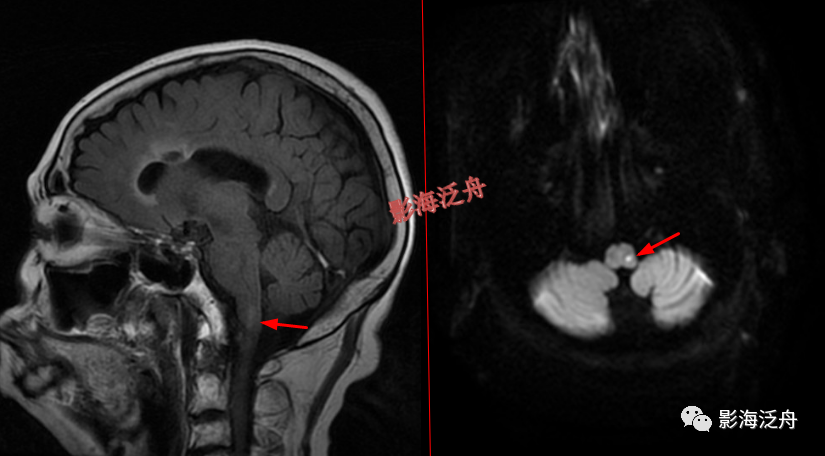

灰质移位,患者既往有癫痫病史。右侧侧脑室前角及左侧侧脑室后角可见异位的灰质结节(红箭),与大脑皮层下的灰质信号一致(绿箭),灰质异位患者多伴有癫痫症状。

透明隔缺如,我自己漏诊过的病例。上面有很多正常的图像可供对比观察。